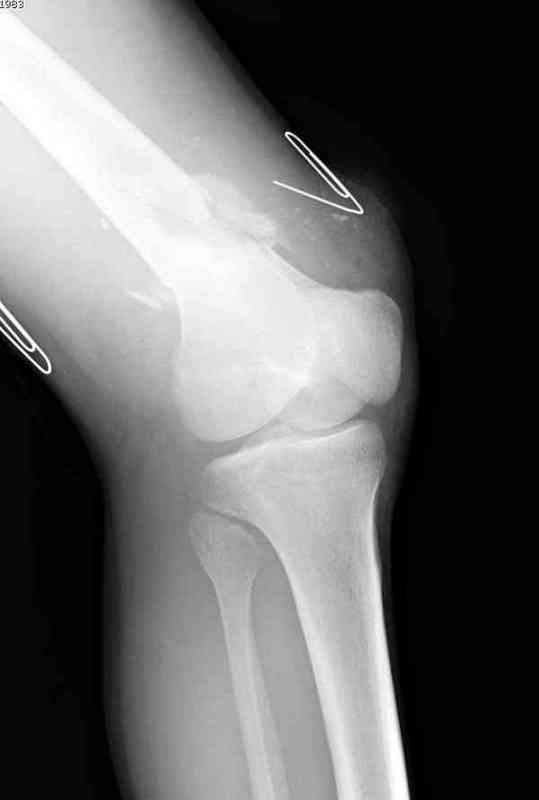

Больная К. с тугим ложным суставом н/3 бедра. Травма в 2005 г.-закрытый перелом, остеосинтез в аппарате Илизарова. В 2006 г. оперирована по поводу несросшегося перелома.

В ноябре 2006 г. демонтаж аппарата, после чего в течении месяца развилась вальгусная деформация. Имеется патологическая подвижность. Объем движений в коленном суставе 180-140. На обсуждение выносятся варианты лечения погружными конструкциями.

The patient with non-union of the distal femur. Trauma in 2005 - closed fracture of the femur, external fixation with Ilizarov apparatus. Non-union. In 2006 open reduction and external fixation with Ilizarov apparatus. In November 2006 the apparatus was removed, after that valgus deformation developed. There is pathological mobility. The knee motion 180-140. We'd like to discuss options of internal fixation.

Надо все-таки разобраться, что там местно - по снимку какое-то как будто сращение на ограниченном участке, но, как пишут, есть и патологическая подвиижность...

Если там сращние или тугой ожный сустав - можно лечить закрыто. Подправить аппаратом и либо заштифтовать, либо пластинку, можно с пластикой, Если дело ближе к болтающемуся ложному суставу - тогда открытая адаптация, аутопластика, как Михаил написал.

Согласен. По снимкам не похоже, чтоб сильно болталось, скорее даже срослось. Клинически с таким коротким фрагментом трудно оценить где "болтается" - в переломе или в суставе. Эффективно смотреть под ЭОПом в режиме скопии.